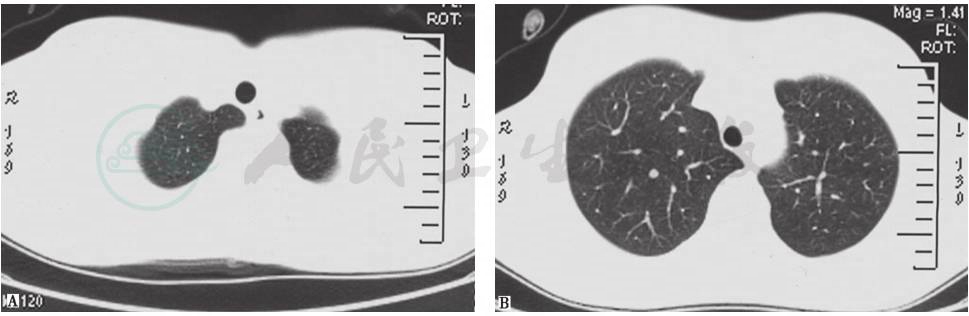

肺动脉增强CT(2015年3月20日):肺动脉宽3.5cm,肺动脉主干左侧内壁略毛糙,可见点状充盈缺损区(图8)。与2015年1月6日胸部CT相比,左肺下叶有新出现的多发病灶,原多发感染病灶大部分有所吸收,原右侧胸腔积液吸收(图9)。

图8 肺动脉增强CT表现(2015-03-20)

图9 胸部CT表现(2015-03-20)